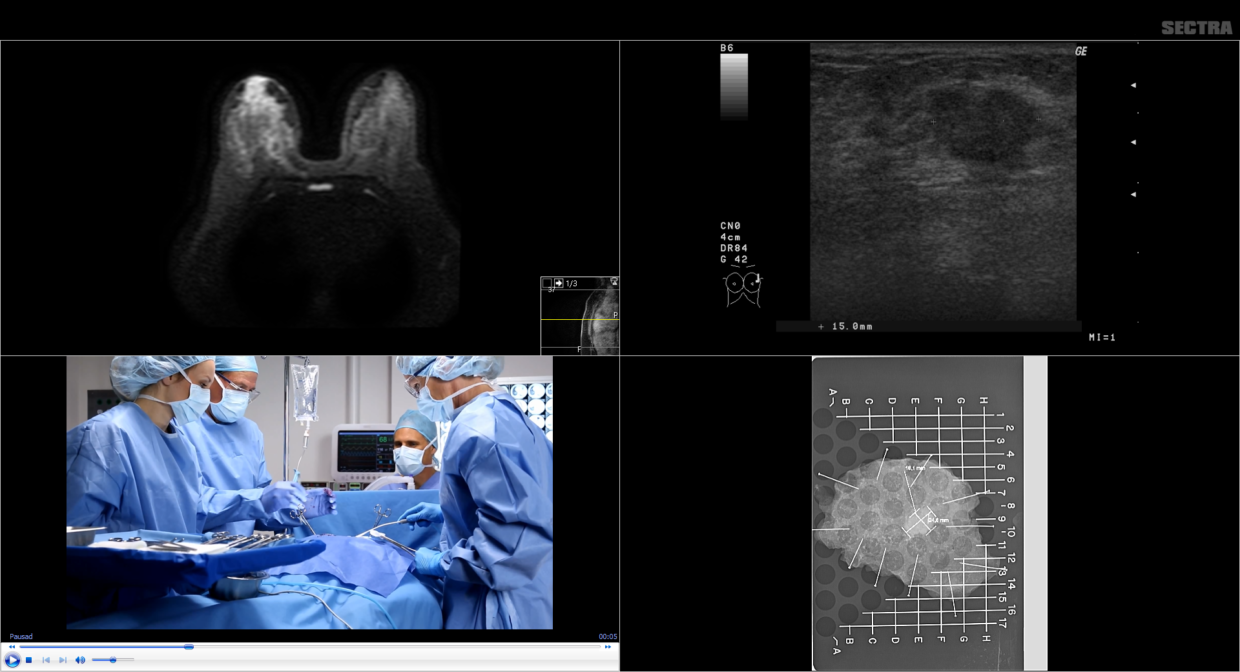

Sectra breast tomosynthesis picture This image demonstrates sectra breast tomosynthesis.

From: seminars in nuclear medicine, 2019. Sectra tomosynthesis t om 2d clinical studies dose, sensistivity and specificity. The agreement includes hologic's flagship 3dimensions digital breast tomosynthesis system. We have designed a mammography system that for the first time combines photon-counting spectral imaging with tomosynthesis. X-ray unit and sectra breast imaging pacs nhsbsp report 0601 may 2006 united kingdom -70% do se reduction, same cancer detection rate and call -back rate future applications: measurin.